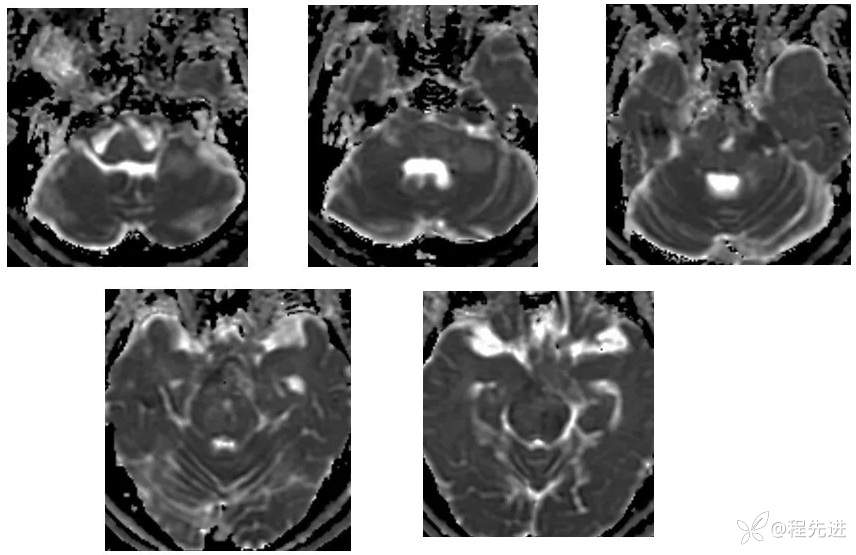

【现病史及既往史】:右眼斜视及视力下降7个月,右眼脸下垂3个月,右眼失明1个月

查体:生命体征平稳,右眼脸下垂,右眼失明,左眼内收位,外展受限,光反应迟钝,左侧角膜反射减弱,左侧听力下降,左面部痛温觉减弱无吞咽困难,无饮食饮水呛咳,伸舌舌尖左偏。